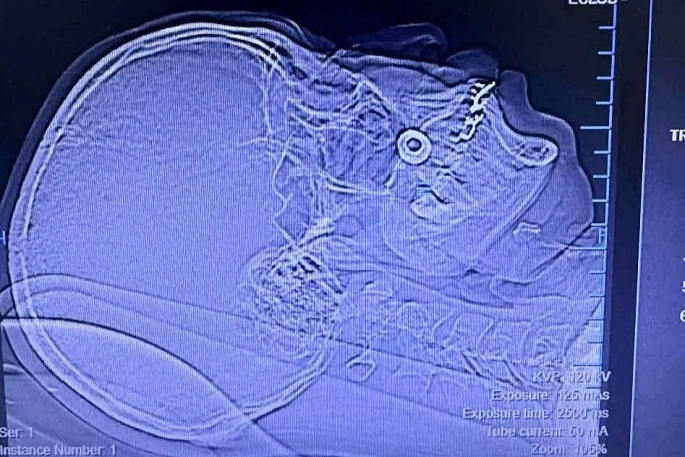

Hình ảnh dị vật kim loại găm trong má bệnh nhân. Ảnh: BVCC

Kết quả thăm khám và chụp chiếu cho thấy có một dị vật kim loại hình tròn đang cắm sâu trong phần mềm vùng má phải, đồng thời gây rạn cung tiếp xương gò má. Nhận định đây là ca bệnh phức tạp, tiềm ẩn nhiều nguy cơ biến chứng nếu không can thiệp kịp thời, các bác sĩ đã tổ chức hội chẩn liên khoa và quyết định tiến hành phẫu thuật.